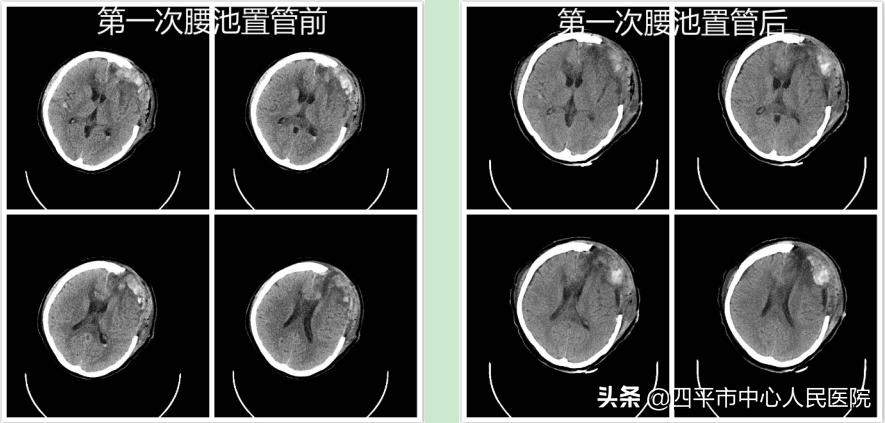

术后患者入重症监护病房,意识障碍减轻,呈浅昏迷状态,头部手术切口和切管切口渗血,发热,刺痛四肢可动。李主任每日查看患者病情变化并指导王野医生换药,每日复查血常规、血凝,积极输血小板和血浆等治疗,每周复查头胸部CT,定期请血液科会诊。经过两周的积极救治,患者终于平稳下来,大约6周时患者逐渐恢复意识。但是病程中患者出现颅内感染,脑积水,严重肺炎,下肢深静脉血栓,癫痫等并发症。针对颅内感染和脑积水,李主任指导经治医生给予患者行脑脊液培养加药敏,选用敏感抗生素,先后给患者做了两次腰大池引流术,持续缓慢引*脑流**脊液,降低颅内压,逐渐恢复了患者脑脊液通路,脑积水症状缓解;针对严重肺炎和深静脉血栓,给予痰培养加药敏等检查并请呼吸内科,血管外科等会诊并相应治疗;经过科室全体医护4个月的积极救治,现患者状态良好,神清语明,记忆力及理解力如常,头部手术切口及气管切口愈合良好,减压张力不高,四肢活动自如,肌力约到5级。